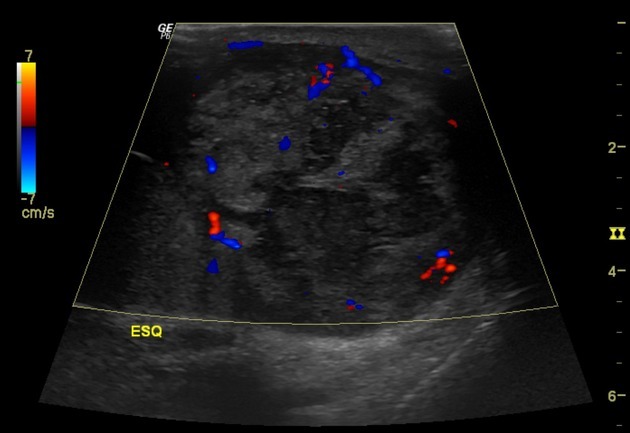

Picture of nephroblstomatosis + Wilms

Screening ultrasound every 3 months until patient turn 8